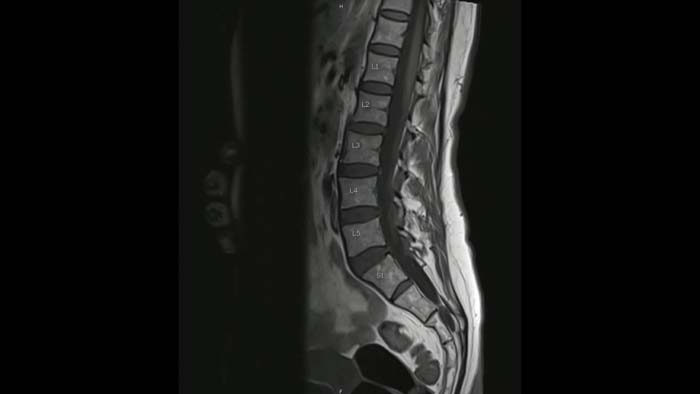

척추관 협착증은 경추관 협착증 또는 요추관 협착증으로 나누어 집니다. 최초 환자가 호소하는 증상을 바탕으로 신경학적인 검사를 통해 방사선학적 검사로 확진됩니다. 퇴행성 여부를 확인하기 위해 전산호 단층촬영, 척추 자기공명영상, 조영술 등이 필요합니다.